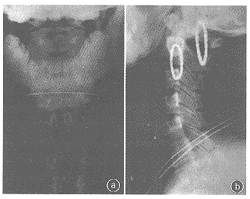

图2C5-6椎间盘脱出。术后3年颈椎正位(a)、侧位(b)

X线片显示骨小梁跨越椎间隙,手术节段已骨性融合

, http://www.100md.com 本组30例,门诊随访24例。经对颈椎正、侧位及屈、伸侧位X线片分析判定,所有植骨融合节段全部融合,移植骨块均无移位、脱落(图2)。但部分患者(17例)有椎体塌陷,颈椎曲度有不同程度的减少;少数患者(1例)出现颈椎后凸畸形。